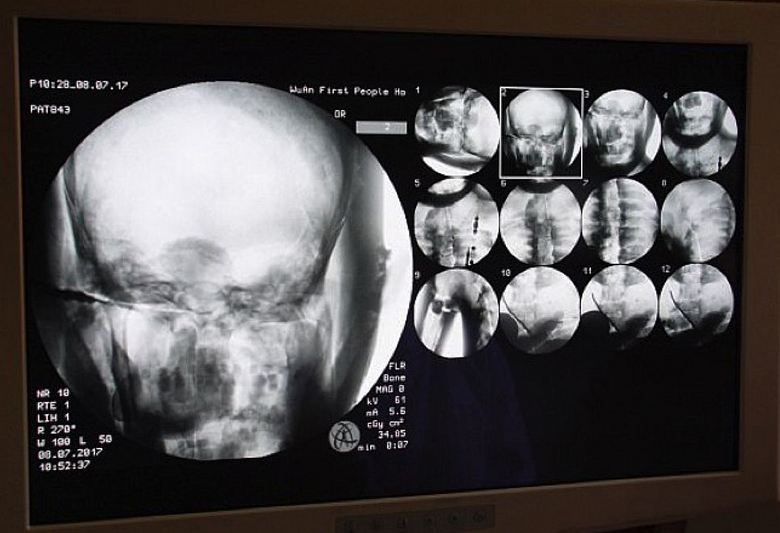

A tudósok önként beleegyeztek, mert maguk is érdekli őket ez az érdekes tanulmány. És ez év július 8-án, közvetlenül a templomban Dinghuit, az ősi buddhista múmia tomográfiáját végezték el szerzetes. Az orvosok idehozták a szükséges felszerelést és eltöltöttek a múmia belső tartalmának beolvasása. Sokkolták kizárólag mindent, azaz nem csak tudósokat, hanem a szerzeteseket is, zarándokok, akik ezen a példátlanul összegyűltek a kolostor számára az esemény természetesen és a média munkatársai. Kiderült, hogy az ízületek, az ezeréves Tsa Xian szerzetes csontjai és fogai olyanok, mint egy élő személy. Sőt, az agya tökéletesen megmaradt.

Hihetetlen – kommentálta Dr. Wu. Yongqing (Wu Yongqing), aki közvetlenül tomográfiát végzett múmiák. Még azt sem tudom elhinni, hogy az ember milyen fő részei több mint ezer évvel ezelőtt balzsamoztak, 2006 – ban megőrizték “egészséges” állapot, még az agy is! De maguk a szerzetesek nem látva semmi természetfeletti ebben, biztosak benne, hogy Tsy mester Xian egyáltalán nem halt meg, egyszerűen belépett a samadhi állapotba amely egy nap biztosan felébred. Végül is egy múmia szkennelése megmutatta: a teste új életre kész